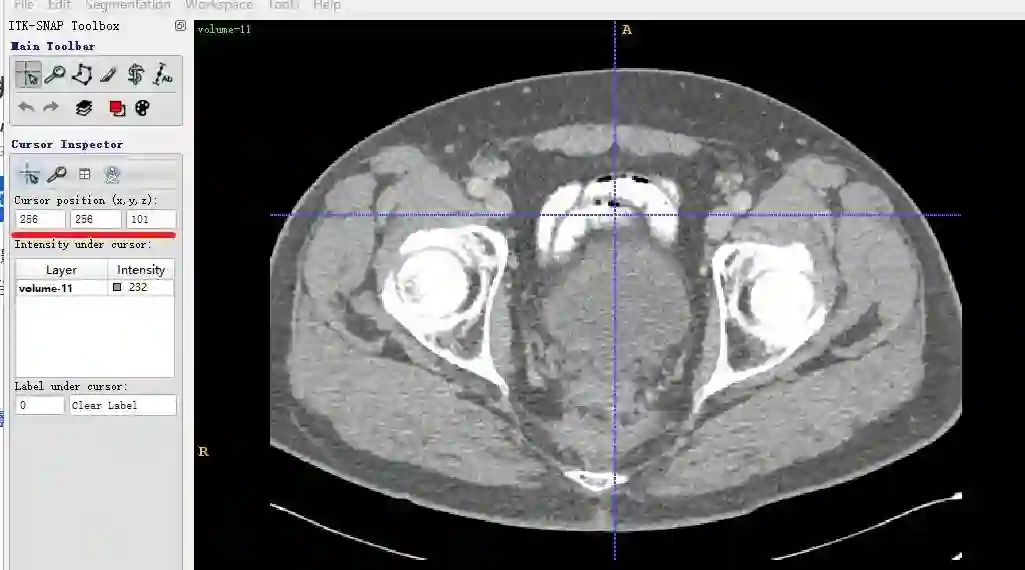

volume-11.nii (466, 512, 512) 232.0

表明该数据shape为(466,512,512),注意对应的顺序是z,x,y。z其实是slice的索引。x和y是某一个slice的宽和高。

z索引为100的plot结果:

同一个slice在ITK-SNAP可视化结果(注意这里(x,y,z=(256,256,101)),因为itk-snap默认从1开始索引):

可以发现,上下两张x轴一样但y轴方向上下翻转了,这是由于matplotlib显示方式不同,但是不会出现读取数据对不齐的问题。